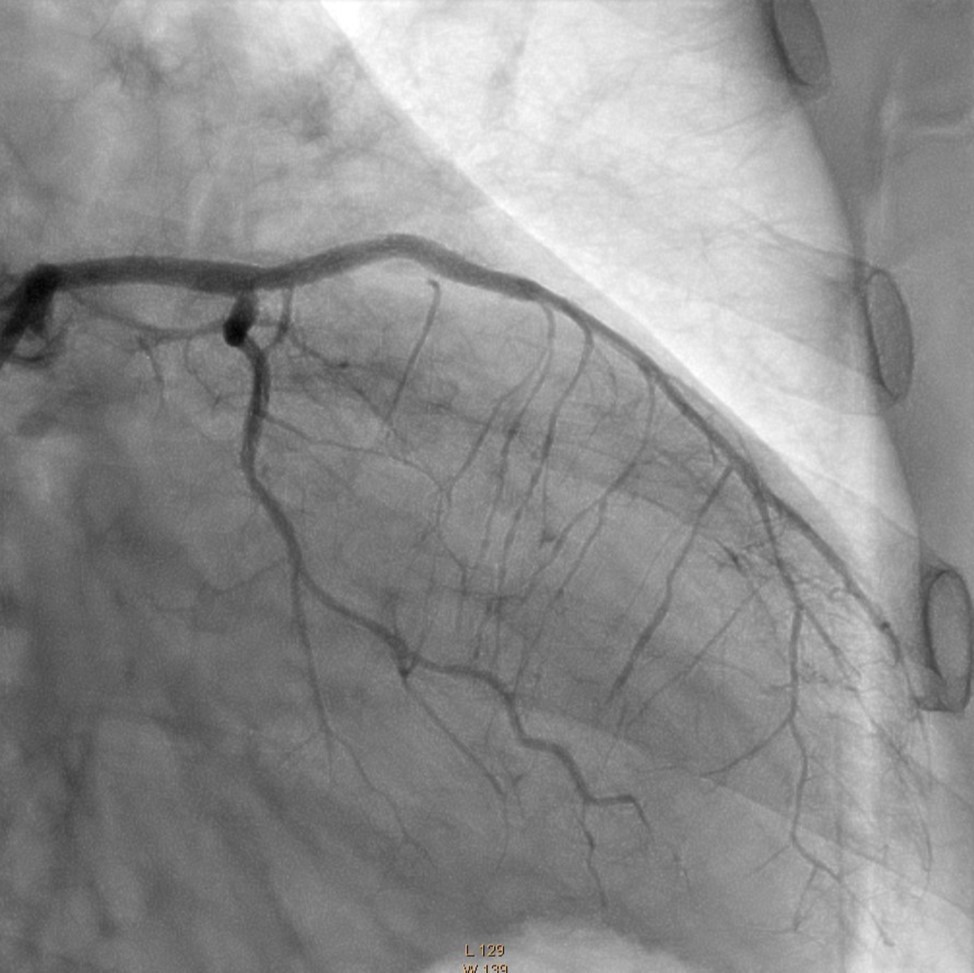

In the first stage, occluded left main and circumflex arteries were recanalized utilizing the support-balloon technique, and CTO wires (Miracle 3™ wire, Abbott Vascular; Runthrough® NS Intermediate wire, Terumo) and balloon pre dilatation was done (Figure 3). In the second stage, the occluded LAD artery was successfully recanalized by utilizing the support-balloon technique, and CTO wires (Figure 3) (due to severe calcinosis the second stage lasted 40 min). In the third stage, LAD artery, CX artery, as well as LMCA and its bifurcation, were stented with 3 drug-eluting stents (Resolute Integrity Zotarolimus DES, Medtronic), the "Culotte Stenting " technique was used for bifurcation stenting (Figure 4), followed by "Kissing Balloon" post-dilatation technique, and finally, proximal optimization technique was performed in the LMCA. The final angiographic image is good, the intervention ended without complications (Figure 5).

Figure 3.LMCA, CX, LAD after recanalization and predilatation

LMCA, CX, LAD after recanalization and predilatation

Figure 5.Left Coronary Artery, final result of the intervention.

Left Coronary Artery, final result of the intervention.